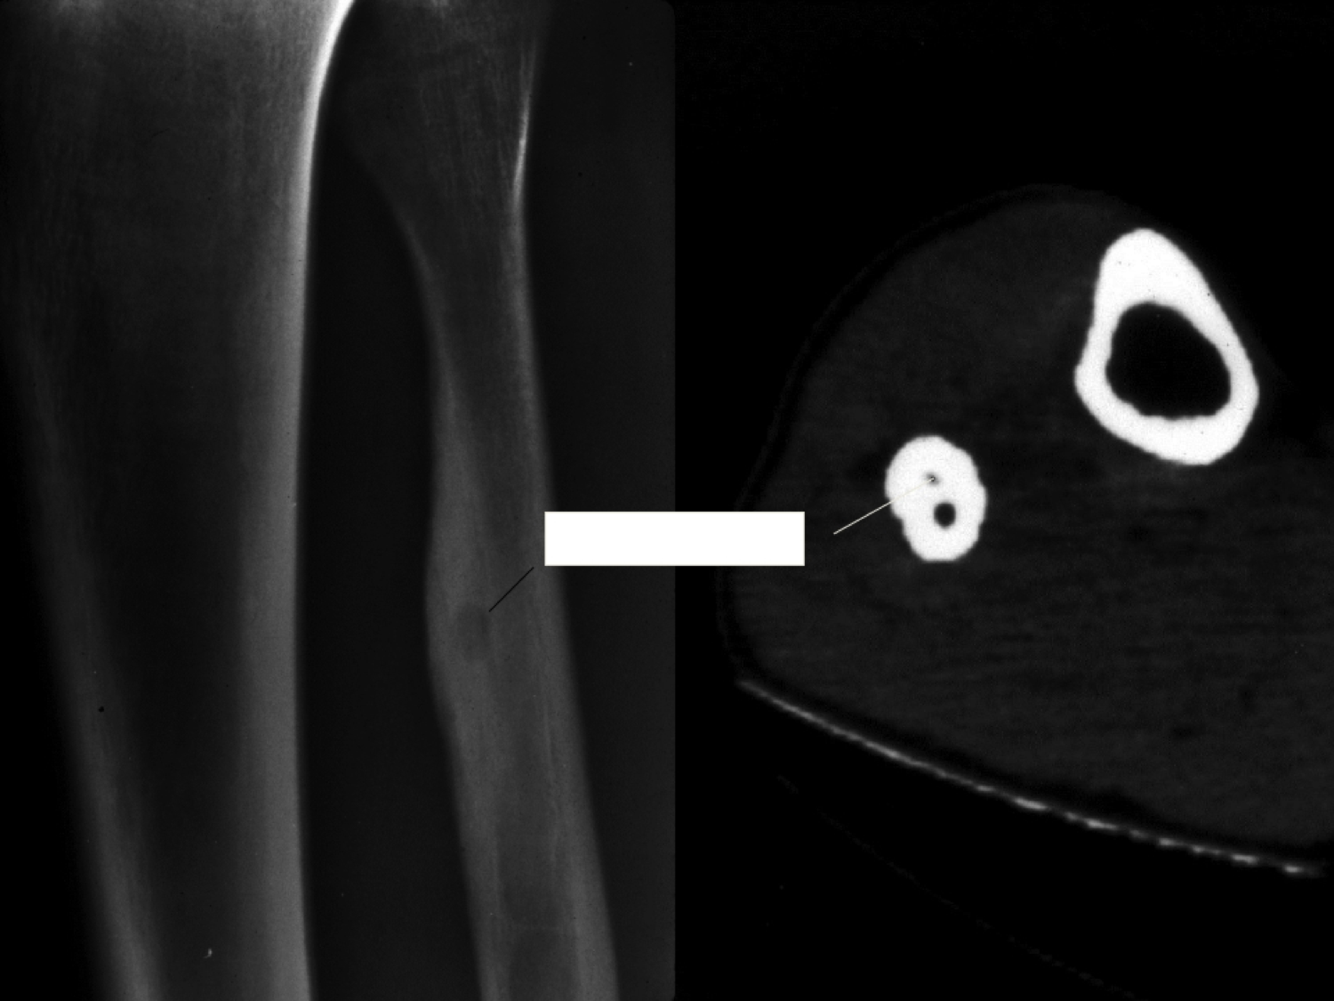

Osteosarcoma

Xray: Codman’s triangle; poorly defined, bone/cortical disruption into soft tissue

What is this?

Cells in osteoid irregular, tripolar mitosis